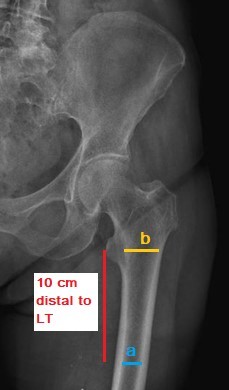

Patients who underwent cemented hip replacement, those treated with non-weight-bearing protocols, those lost to follow-up, and those who experienced post-operative prosthetic joint infections or died during the follow-up period were excluded from this study. The minimum follow-up duration was 21 days, while the maximum was extended to 6 months. Preoperative variables included age, gender, and ASA score. The primary objective was to divide the cohort into two groups based on femoral stem subsidence: One group with a low rate of subsidence (0–4.99 mm) and another with a high rate of subsidence (>5 mm). Each group was further subdivided according to the proximal femur morphology as classified by the Dorr classification. The Dorr classification assesses the quality of the proximal femur based on radiographic, biochemical, and histological characteristics. Thick and well-defined cortices characterize type A, while Type B indicates bone loss from the medial and posterior cortices, leading to a broader diaphyseal canal, and Type C reflects significant loss of the medial and posterior cortices, resulting in decreased bony definition of the cortices [15]. In this study, we assessed the Dorr classification through quantitative measurements by calculating the canal diameter 10 cm distal to the lesser trochanter and dividing it by the inner canal diameter at the mid-portion of the lesser trochanter [15] (Fig. 2). A ratio of <0.5 mm was classified as Dorr type A, a ratio between 0.5 and 0.75 mm as type B, and a ratio >0.75 mm as type C.

Figure 2: Anteroposterior radiograph of the left hip illustrates the Dorr criteria calculation (a/b = ratio for Dorr criteria).